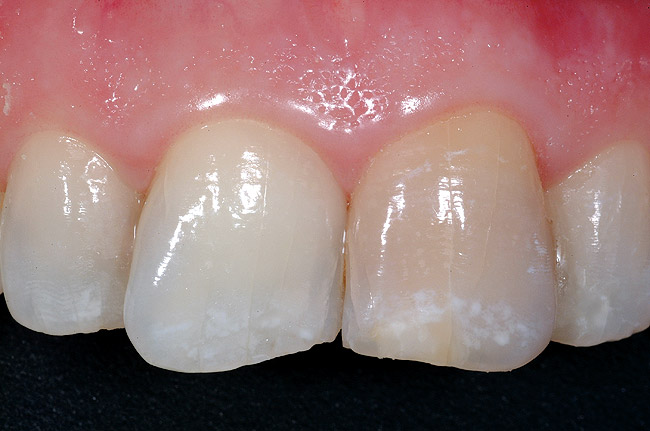

The feature case of this article, highlighted in Figure 13 through Figure 24, demonstrates a comprehensive shift in many aspects of endodontic access. The calcified central incisor ( Figure 13) of a 42-year-old woman was treatment planned for elective endodontics to facilitate internal bleaching for esthetic reasons. The preoperative radiograph demonstrated almost complete obliteration of the pulp, except for a small pouch in the center of the root. Referring these challenging cases to a microscopeequipped endodontist should always be considered. However, many well-trained general dentists attempt these difficult cases, and most dentists routinely deal with partially calcified cases. Still, the concepts forwarded in this case can be employed as indicated in every endodontic access treatment.

The resultant cavosurface outline is quite long and fairly narrow for the calcified tooth, and creates better potential for accuracy ( Figure 18 and Figure 19). A final view of the access in Figure 20 shows the orientation of the palatal–incisal notch and the dentinal map, which is encountered as early as possible. The radiographic sequence ( Figure 21, Figure 22, Figure 23 and Figure 24) teaches a new concept in accessing calcified canals, that of radiographs taken using the pointing quality of a conical bur to assess direction and position of the access cavity. Corrective steps can then be taken to avoid gouging or perforation. In the past, only endodontic files have been used as metallic (radiopaque) radiographic markers. The snug fit of a conical bur as opposed to the loose fit of a round bur facilitates the use of the bur in taking "bur instrument films."

The old bias of horizontal primary access that intersects the dentinal map in the middle of the crown deprives the clinician of this incredibly useful and important landmark, that of the old pulp horn. Additionally, the old bias requires a 90° turn from horizontal to vertical, which invariably leads to facial gouging and other more subtle problems. Each step of the access should lay a foundation for success and prevention of gouging. There are five critical biases and the accompanying changed access principles demonstrated in the feature case, which are outlined in Table 1.